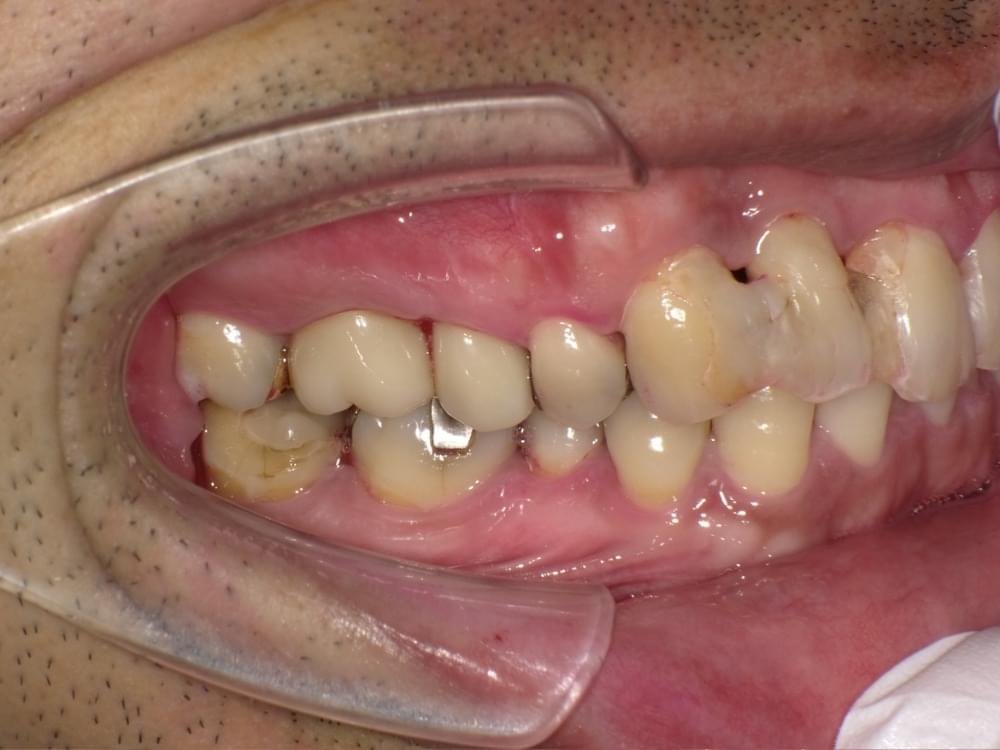

歯周病治療プログラムの治療例5

治療の概要

治療内容

行動科学に基づき、「自分の歯は自分で守る」という意識改革や行動変容を促しながら、スケーリングや歯ブラシ・フロス指導を行いました。

治療期間・回数・時間

1.5ヶ月・5回・計5時間

費用

29,500円+税

リスク・副作用

歯肉の痛み・出血